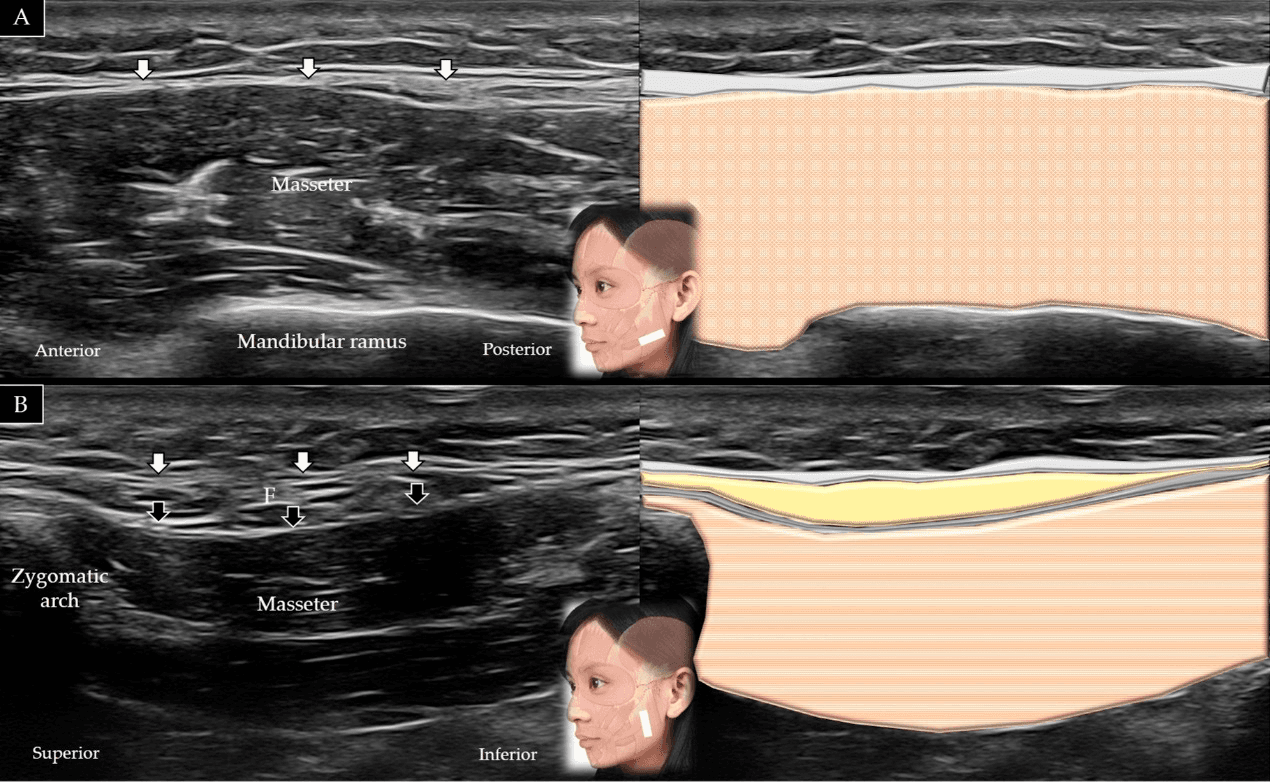

보툴리눔독소 - 교근(masseter)의 단축(A)과 장축(B)에 대한 초음파 스캔 및 도식적 표현입니다. 흰색 화살표와 회색 음영은 표재성 근건막계(super Figure 15. 교근(masseter)의 단축(A)과 장축(B)에 대한 초음파 스캔 및 도식적 표현입니다. 흰색 화살표와 회색 음영은 표재성 근건막계(superficial musculo-aponeurotic system), 검은색 화살표와 짙은 회색 음영은 이하선-교근근막(parotid-masseteric fascia), F와 노란색 음영은 지방(fat), 갈색 음영은 교근을 나타냅니다.